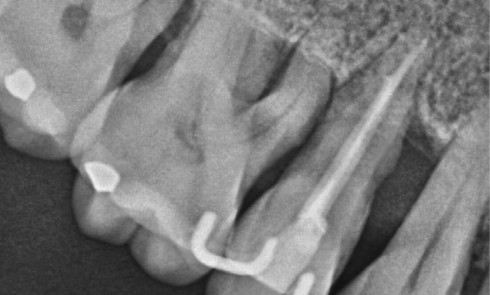

Endodontie

Article réservé à nos abonnés Les concepts actuels en microchirurgie endodontique

Les échecs endodontiques sont principalement causés par la persistance de micro-organismes au sein du système canalaire [1]. Le retraitement non...